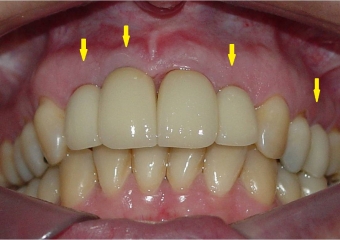

Dentes individuais em porcelana

Sorriso final, do caso terminado em abril de 2013